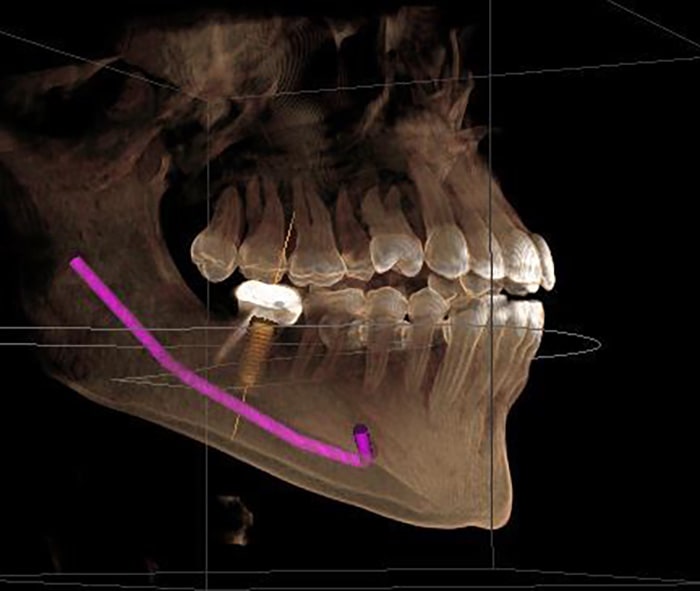

At Kamala Dental Super Speciality Hospital, Thiruvananthapuram, we utilize advanced Cone Beam Computed Tomography (CBCT) and 3D scanning technologies to obtain highly detailed images of your teeth, jaws, nerves, and surrounding structures. These cutting-edge tools empower our team to diagnose more accurately and plan treatments with greater precision - giving you safer, more predictable outcomes.

- Detailed, Clear Views: CBCT produces 3D images of bone anatomy, root canals, jaw joints, sinuses, and nerve pathways - far more informative than traditional 2D X-rays.

- Personalized Treatment Planning: Create precise surgical guides, implant placements, and orthodontic strategies based on your unique anatomy.

- Dental implant planning & placement

- Surgical planning for extractions, bone grafts, and sinus lifts